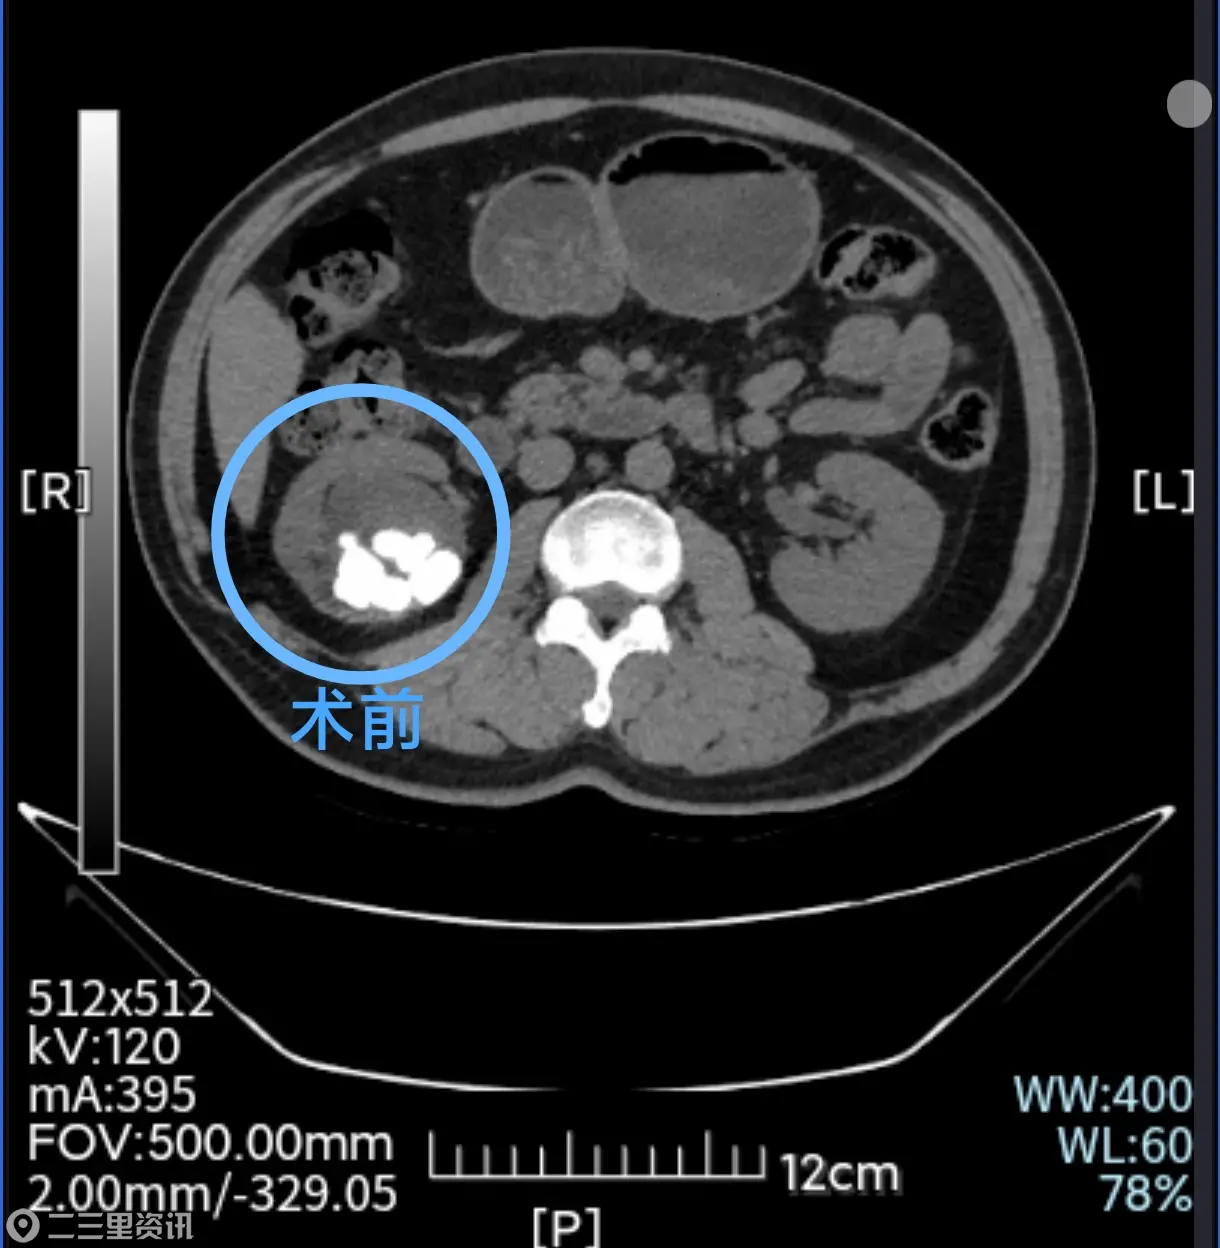

早在20年前,于先生在体检时就发现患有肾结石,当时接受了外科开放取石手术治疗,近期几个月上厕所持续出现血尿,CT检查显示肾盂复杂多发结石,最大的有2.1×2.0cm大小。

随后泌尿外科结石组张少杰团队为于先生实施了“无管化”的经皮肾镜激光碎石取石术(tubeless PCNL),手术创口仅1厘米,术中缝合一针并贴上创可贴,次日于先生即可正常下床活动,复查显示结石已彻底清除,对此于先生感觉非常满意,入院4天后即康复出院。